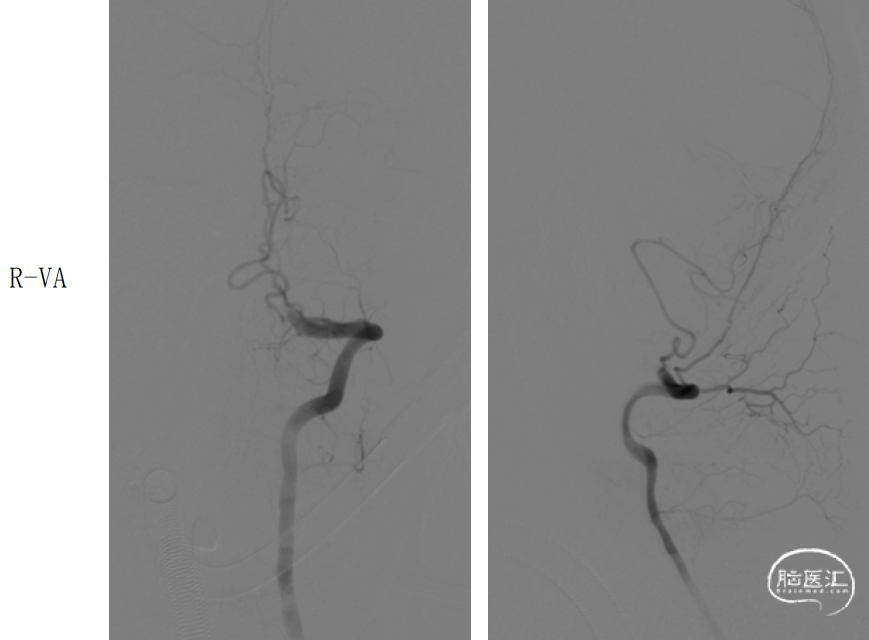

穿刺留置8F动脉鞘,以5F单弯导管行左侧椎动脉造影示:左侧椎动脉PICA以远闭塞。

路图下,在泥鳅导丝导引下将8FGuiding置于左侧椎动脉V2,将Catalyst5 0.058in*132cm沿导引导管置于左侧椎动脉PICA以远闭塞处。

造影示:基底动脉下段可见重度狭窄,远端闭塞,将Catalyst5缓慢通过狭窄处置于闭塞处,负压抽吸可见抽出暗红色血栓,复查造影基底动脉下段重度狭窄,远端显影良好,双侧大脑后动脉、双侧小脑上动脉显影良好,mTICI分级:3级。

DSA:R-V4闭塞

DSA:L-V4闭塞